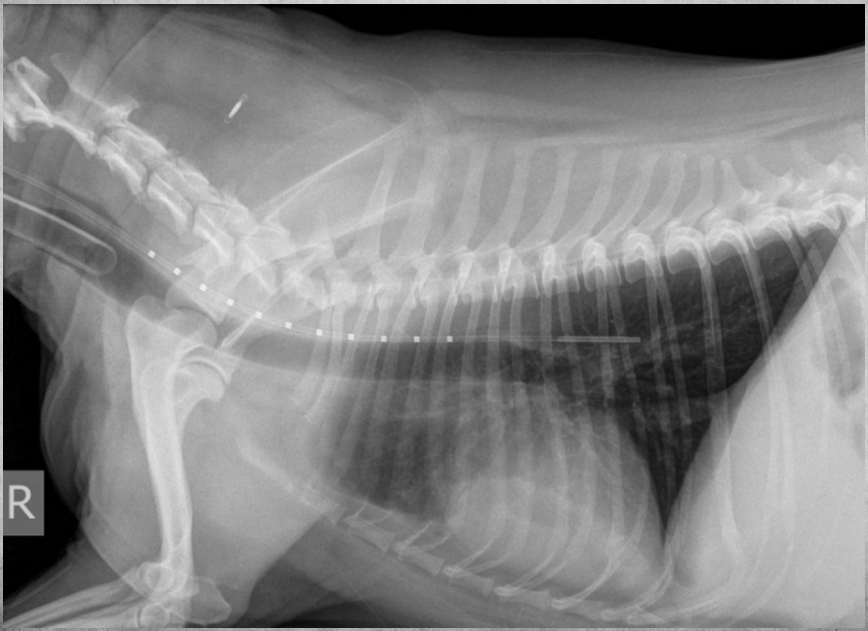

● 12 yo dog

● Coughing for 2 months

alveolar pattern caudodorsally (black tree visible)

fat in ventral thorax

cardiac silhouette lifted and rounded, maybe free fluid

on VD: mass effect